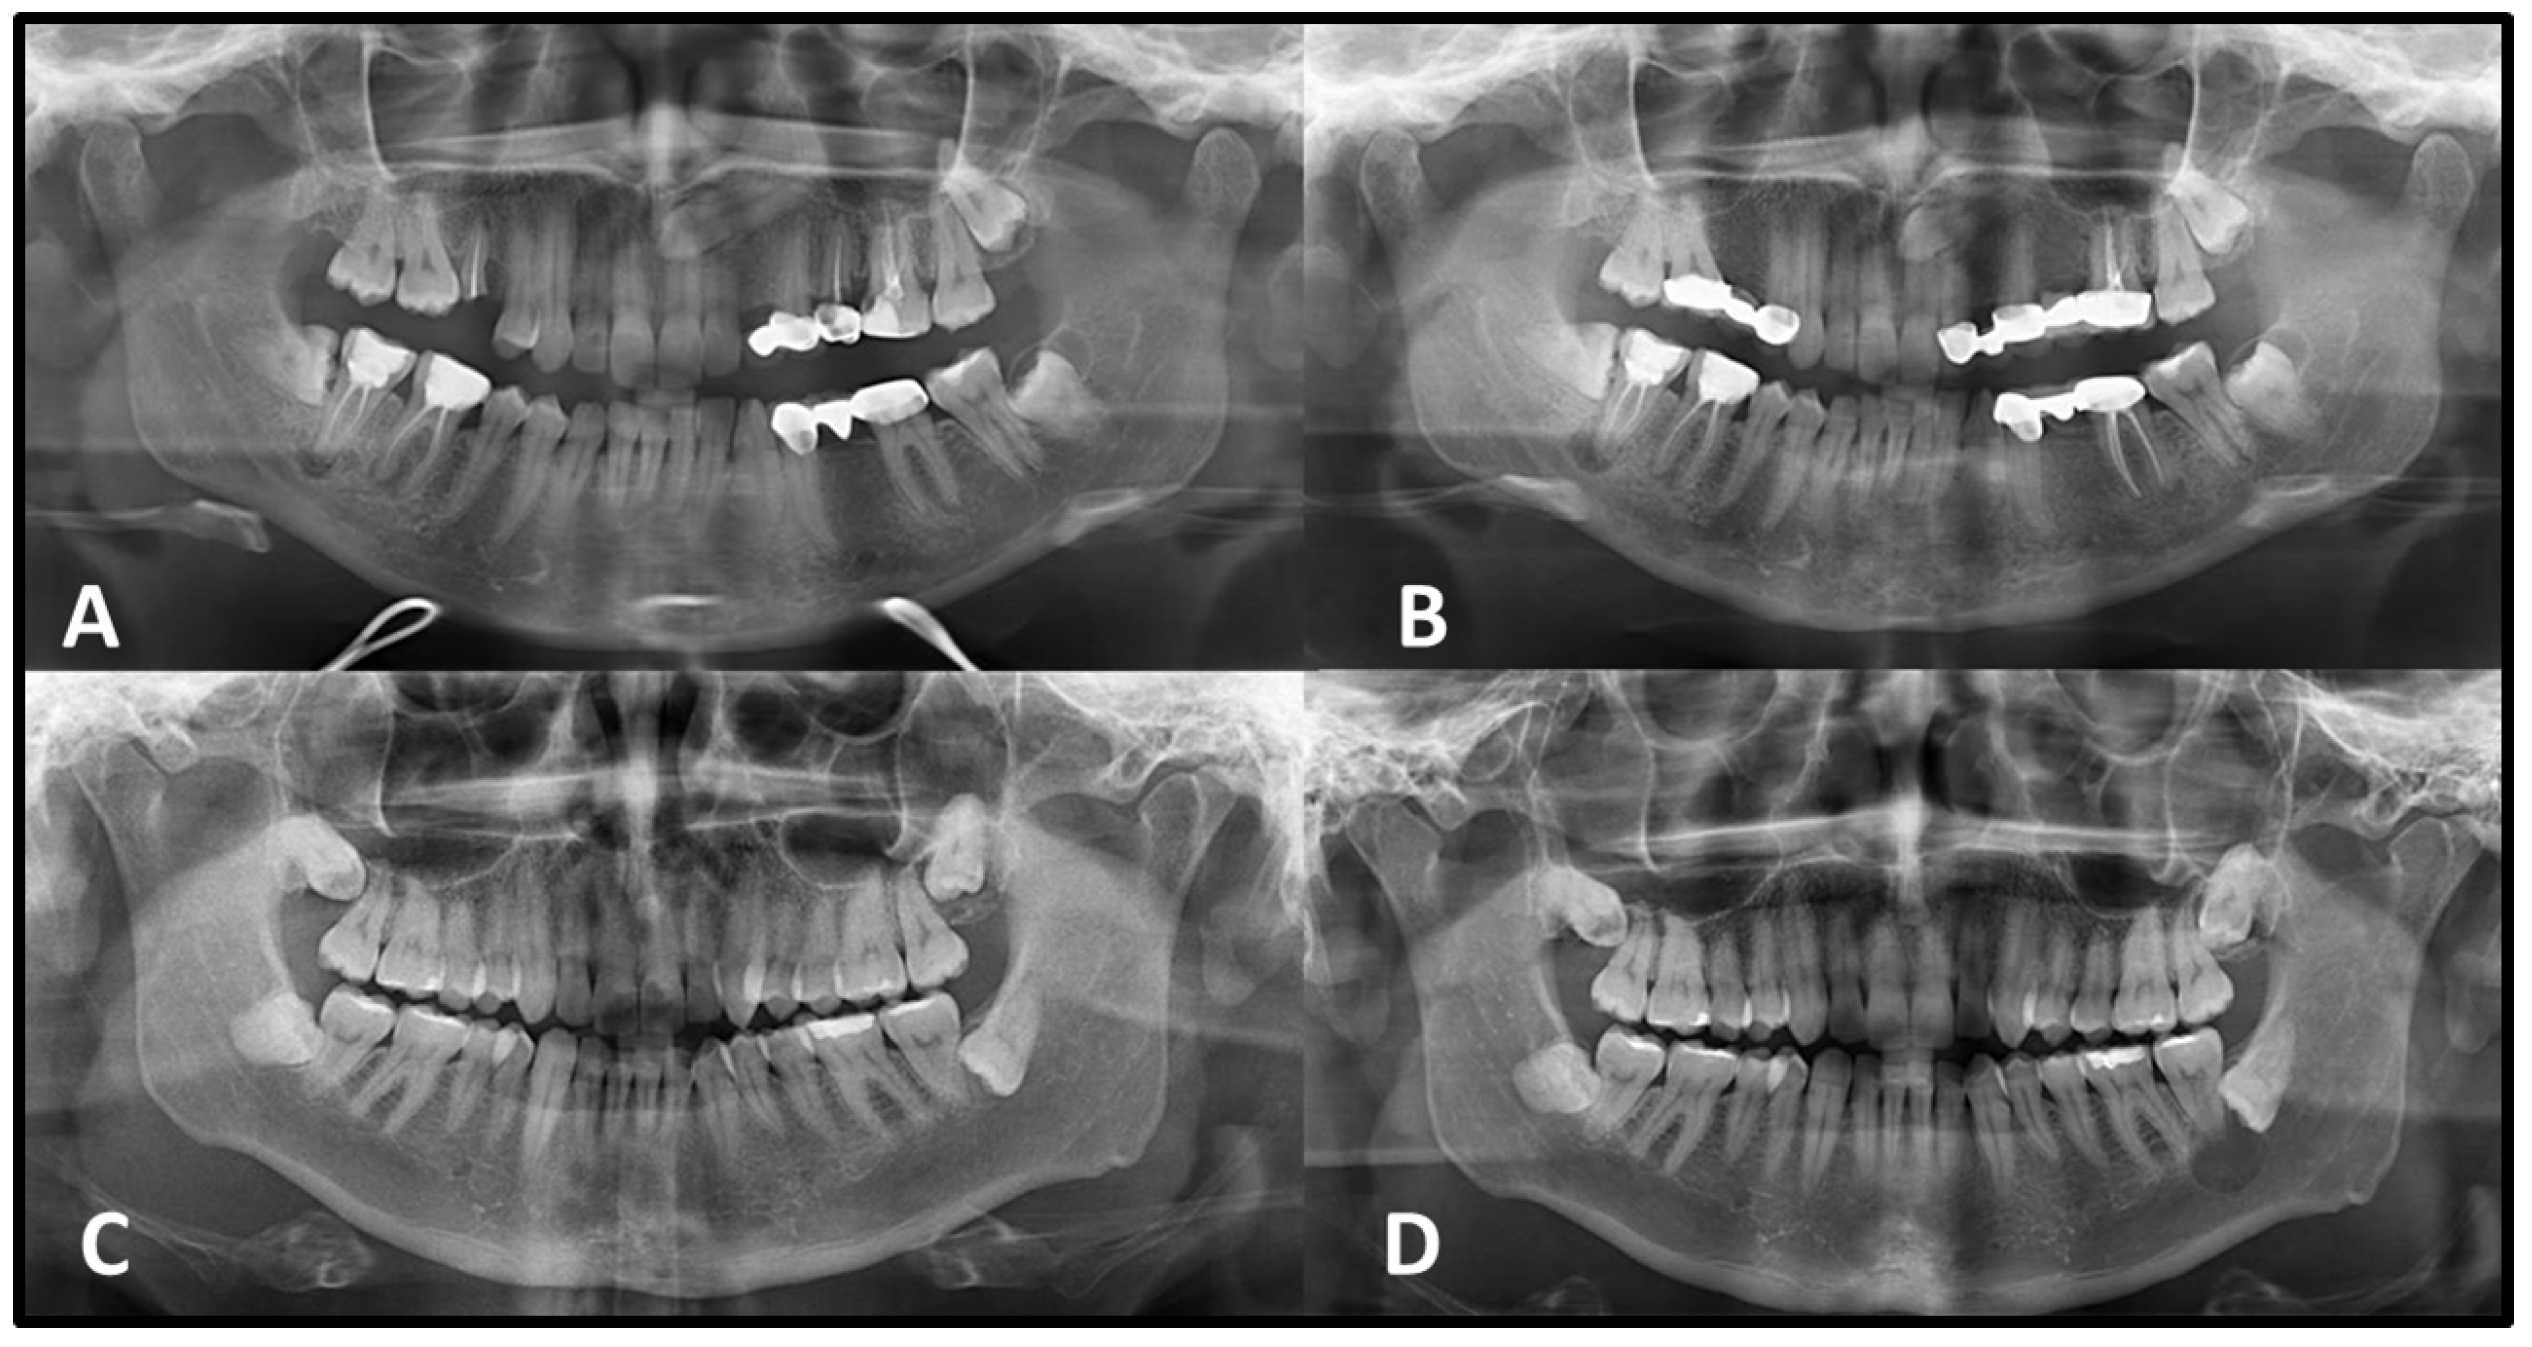

Statistically significant differences were observed in both vertical and horizontal dimensional changes between lesions with corticated and non-corticated borders on the initial PANs (

p < 0.05). Lesions lacking corticated margins demonstrated a greater percentage of growth over time compared to those with corticated boundaries (

Table 3,

Figure 2 and

Figure 3).

Cysts that originate within bone typically exhibit well-defined corticated margins, often represented by a thin radiopaque line; however, secondary infection can alter this appearance, rendering the borders thicker, sclerotic, or poorly defined. Generally, lesions with well-defined margins are considered benign, while ill-defined margins tend to suggest more aggressive, inflammatory, or neoplastic processes [

7]. A radiographic pattern observed in this study was the progressive cortication of lesion margins over time, particularly among lesions that initially presented without corticated borders. This trend was most frequently observed in radicular cysts, many of which developed corticated margins during follow-up. Lesions with corticated borders on the initial PAN tended to show smaller dimensional changes, whereas those lacking cortication at baseline generally exhibited greater enlargement and more frequent development of partial or complete cortication over time. These radiographic patterns suggest that the presence or absence of cortication may be associated with different trajectories of radiographic change; however, these observations reflect radiographic changes only; no causal or biological interpretations were inferred from these findings. Additionally, changes in the appearance of cortication on PANs may be influenced not only by biological processes but also by technical factors such as projection differences, unequal magnification and geometric distortion, patient positioning, and measurement variability inherent to two-dimensional imaging [

7].